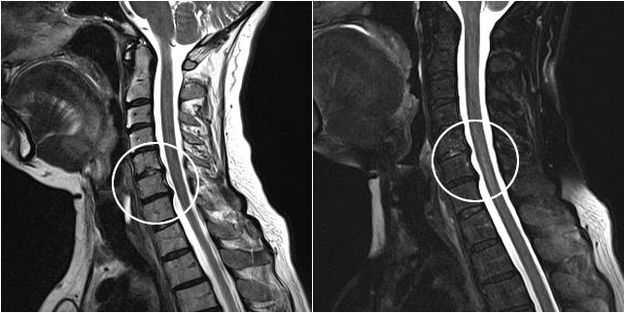

Modern diagnostic methods include MRI and CT, which make it possible to most accurately examine the processes of destruction of cartilage and bone tissue.Also, using this technique it is convenient to diagnose hernias and other soft tissue defects near the source of the disease.